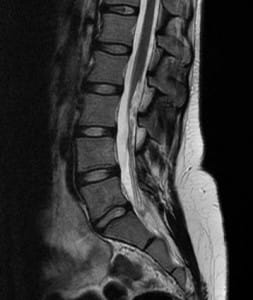

La resonancia magnética nuclear (RMN) es un examen médico no invasivo que ayuda a que los médicos diagnostiquen y traten enfermedades.Nuestro servicio cuenta con tecnología de vanguardia, con software especial para cada región del cuerpo, en especial para columna, contamos con un programa llamado COMPOSING que nos permite obtener los tres tramos de la columna en una solo adquisición.Las imágenes detalladas obtenidas con la RMN les permiten a los médicos evaluar mejor varias partes del cuerpo y determinar la presencia de ciertas enfermedades que no se podrían evaluar adecuadamente con otros métodos por imágenes como los rayos X, el ultrasonido o las tomografías axiales computarizadas (también denominadas TC o exploración por TAC).El examen de RMN de columna muestra la anatomía de las vértebras que conforman la columna, así como los discos, la médula espinal y los espacios entre las vértebras por donde pasan los nervios.En la actualidad, la RMN es el examen de diagnóstico por imágenes más sensible que se utiliza en la práctica médica de rutina para visualizar la columna.

- Evaluar los discos—protuberantes, degenerativos o hernia de disco intervertebral—una causa común de dolor lumbar y ciática.

- Evaluar los nervios comprimidos (pinzados) e inflamados.

- Explorar las posibles causas en pacientes con dolor lumbar (por ejemplo, fractura de compresión).

- Visualizar la infección de la columna o tumores que aparecen en la columna o se han extendido a ella.

- Las imágenes de RMN de la columna son más claras y detalladas que las que se obtienen con otros métodos de diagnóstico por imágenes. Esto hace de la RMN una herramienta valiosísima para el diagnóstico y evaluación tempranos de muchas patologías de la columna, incluyendo tumores.

- La RMN muestra anomalías, lesiones y enfermedades en la zona de la columna que no pueden visualizarse con otros métodos de diagnóstico por imágenes.

- La RMN es muy útil para evaluar lesiones en la columna. Es particularmente útil para diagnosticar o descartar la compresión de la médula espinal cuando el examen clínico revela debilidad muscular o parálisis.

- La RMN puede detectar pequeños cambios en la columna vertebral que podrían ser una infección o un tumor en etapa temprana. El procedimiento es mejor que la exploración por TAC para la evaluación de tumores, abscesos y otras masas de tejido blando cerca de la médula espinal.